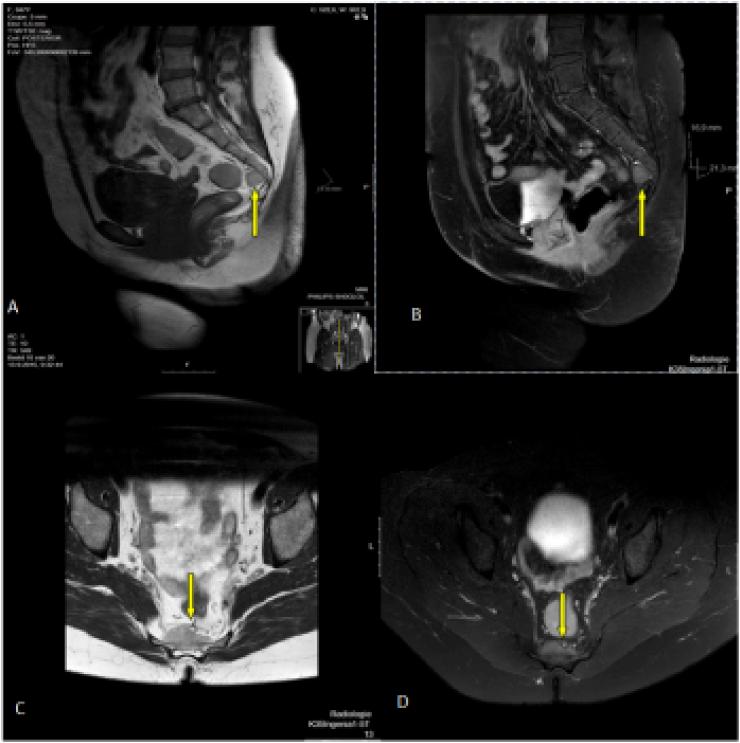

PRESENTATION OF CASE

We report two cases of presacral myelolipomas. The first is a 48-year-old female presenting with atypical back pain, found to have a mass in her presacral region with a size of 3,3 cm. The second case is a 59-year-old female, who presented for evaluation of a hip fracture, found to have a 4,7 cm presacral lesion. Both presacral myelolipomas were discovered incidentally and were confirmed by percutaneous guided fine-needle aspiration biopsy. Both were treated conservatively.

我们报告两例骶前髓脂肪瘤。第一例是一名48岁女性,表现为非典型背痛,发现骶前区域有一个大小为3.3厘米的肿块。第二例是一名59岁女性,因髋部骨折前来评估,发现有一个4.7厘米的骶前病变。这两例骶前髓脂肪瘤均为偶然发现,并经皮引导细针穿刺活检确诊。两例均采用保守治疗。